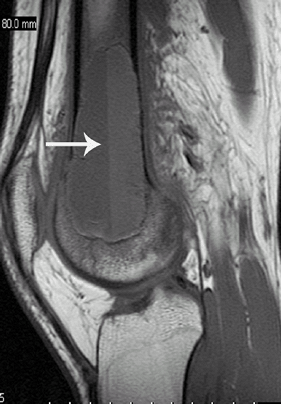

Collateral ligament tears are detected by fluid or contrast through the ligament, best seen on coronal oblique views (Fig. 1).

Fig. 1. Coronal images of the MCL. A: 3D gradient echo showing the normal anterior bundle of the MCL (arrow). B: Fat-suppressed T2-weighted images showing a completely torn distal attachment. -